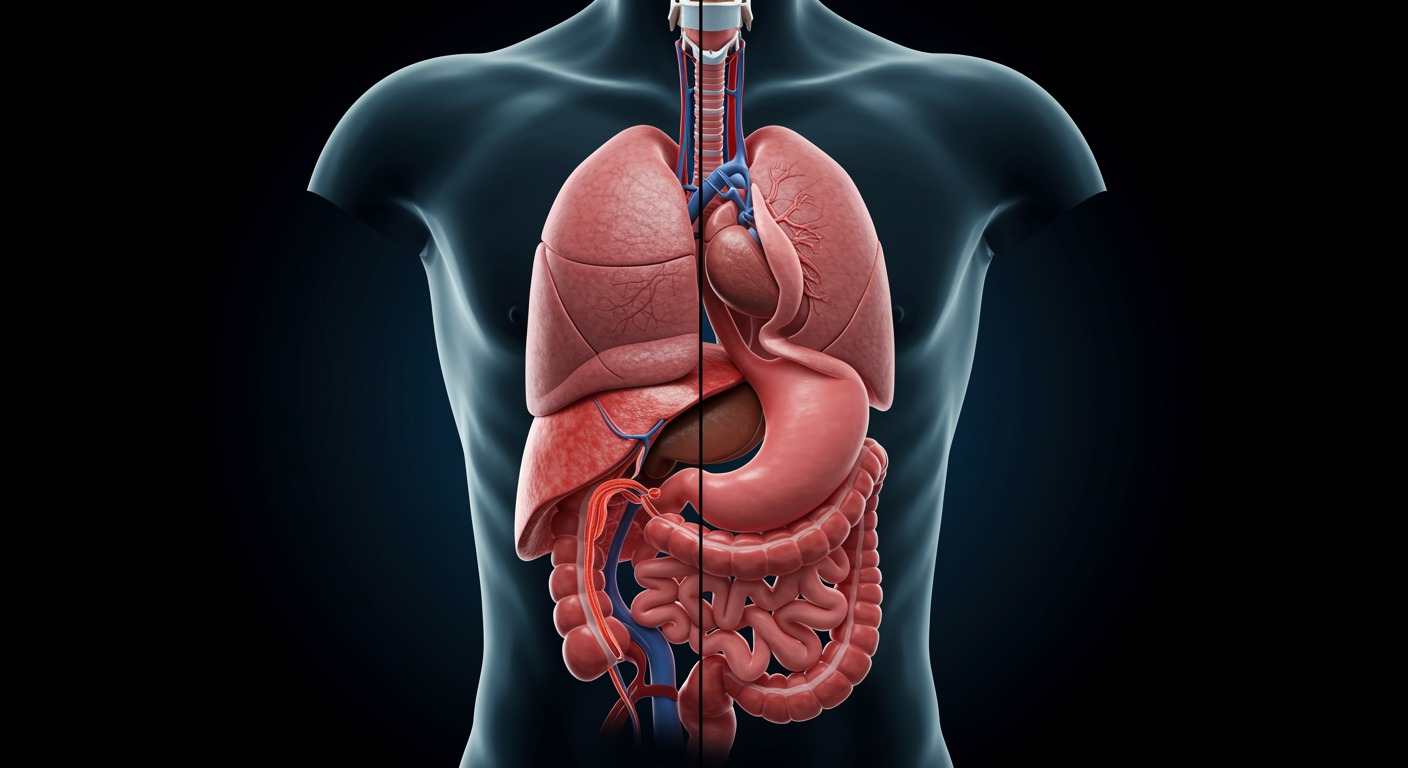

The gastrointestinal system—from mouth to colon—is responsible for digestion, nutrient absorption, immune function, and even neurotransmitter production. As the interface between the external environment and the internal body, gut health has far-reaching effects on overall wellness.